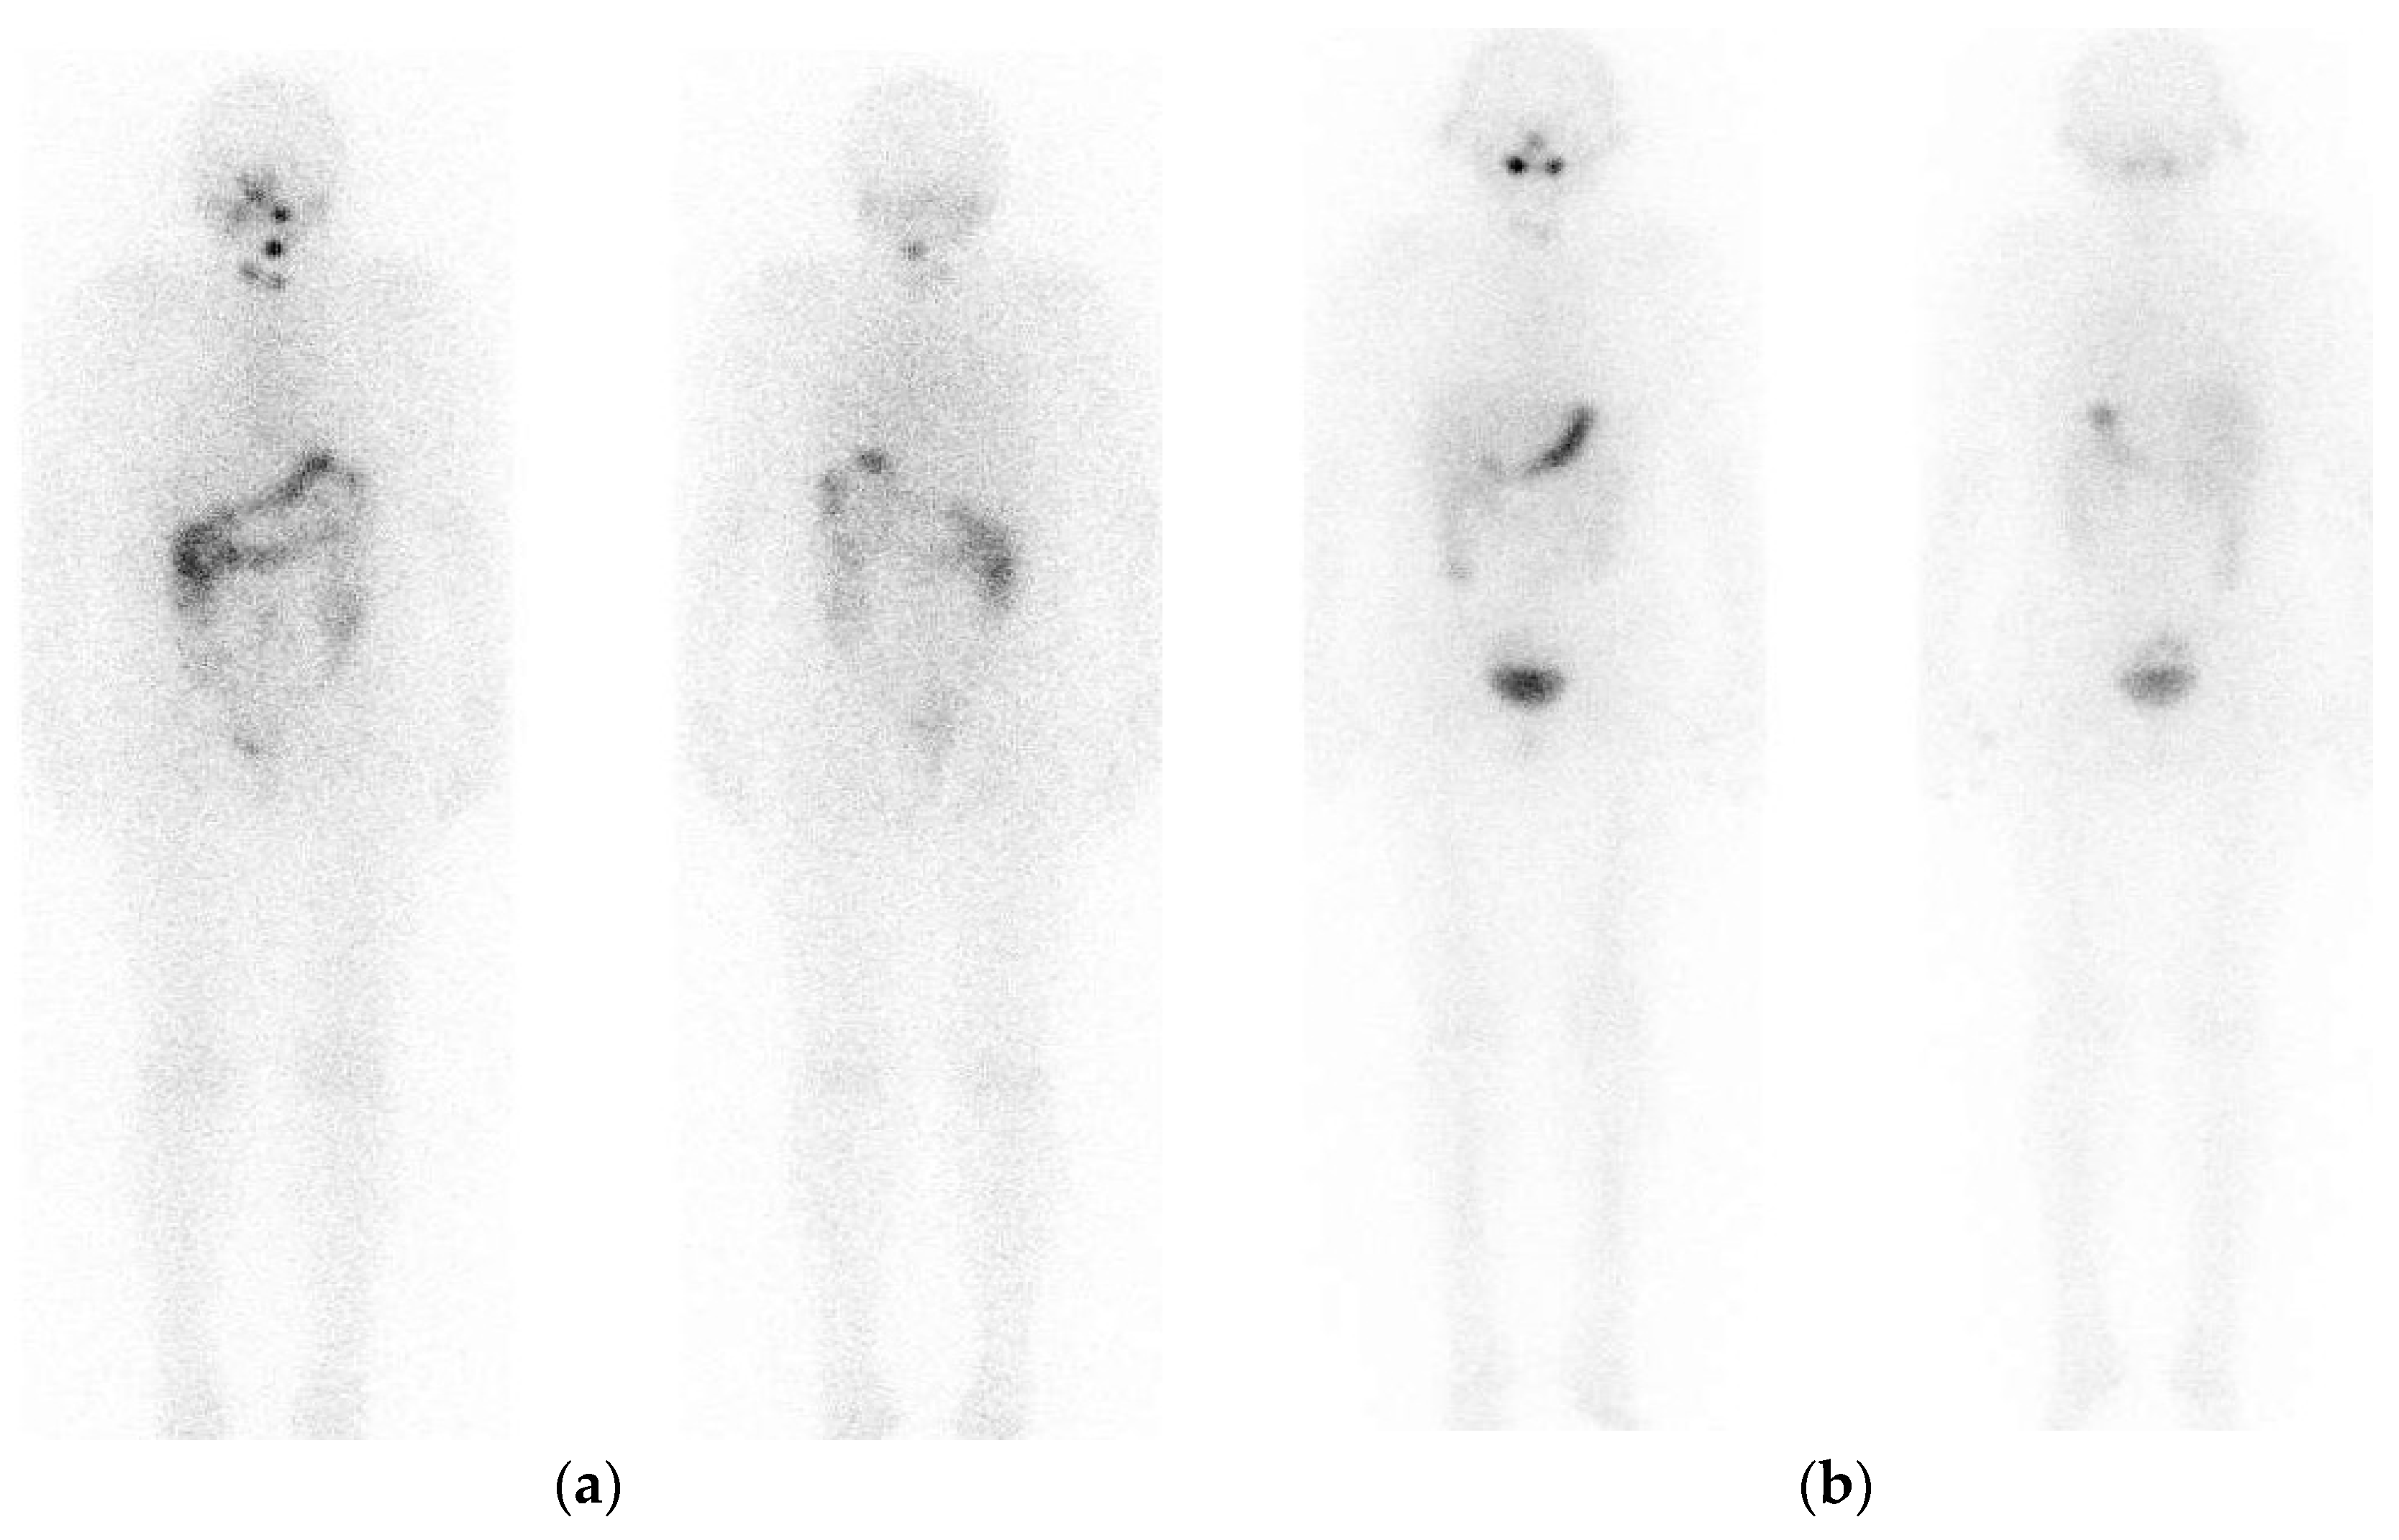

2. Pre-Treatment Whole-Body Imaging

3. Post-Treatment Whole-Body Imaging